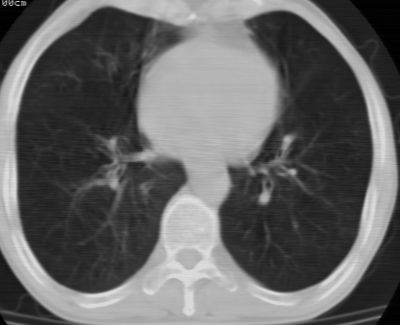

标题: CT24783:m71,既往肺心病史3年,现咳嗽,憋喘。 [打印本页]

标题: CT24783:m71,既往肺心病史3年,现咳嗽,憋喘。

1)左肺上叶周围型肺癌可能。2)两肺全小叶型肺气肿。

左上周围型肺癌,全小叶型肺气肿。